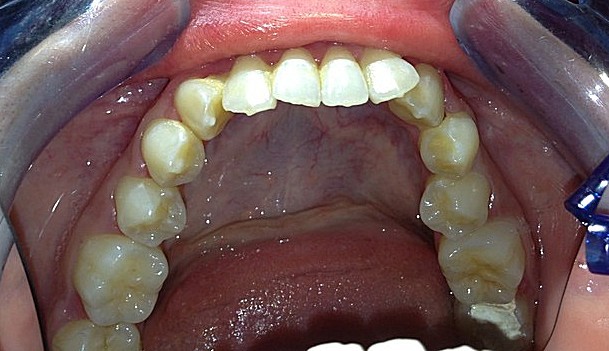

I risultati Arrivano e si vedono.

Uno dei nostri ultimi cambiamenti radicali.Il tuo sorriso può essere più vicino di quello che immagini

Total Dental MakeOver presso lo studio di implantologia sicilia del dott Gabriele Mirabella.

Scopri come era questa bocca prima del trattamento presso la clinica dentistica del Dott. Gabriele Mirabella

clicca se vuoi vedere il quadro clinico iniziale e vedrai che anche tu puoi avere il sorriso che hai sempre desiderato